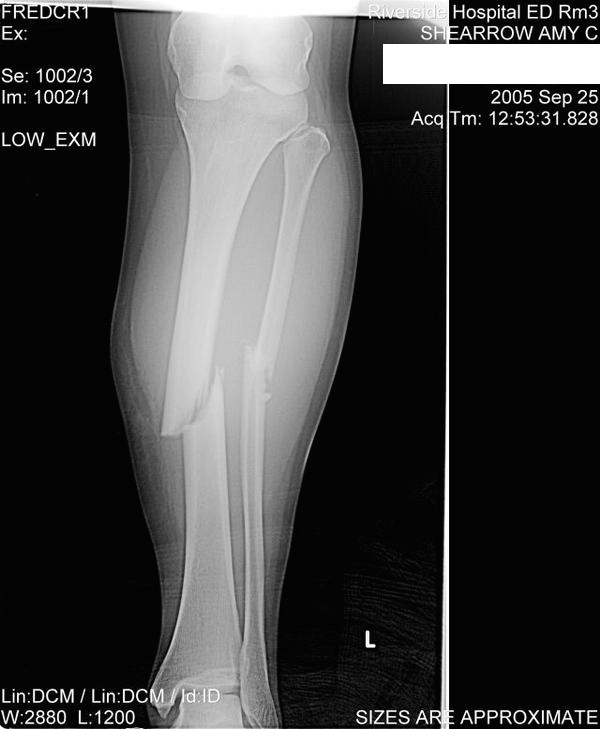

We started playing and it was ALMOST the end of the game when I saw it.  The other team had possession.  They ran their play and it looked like the quarter back was throwing it to someone right next to me but there was nobody there (that I could see).  WOO HOO! I was going to get an interception! I went for it. I went for it hard. ALSO, a guy from the other team who was behind me went for it.  I was moving sideways towards it. He dove for it. I don’t know who ended up getting it because when he landed, he landed on my left leg. My leg went under him but my body went over him and SNAP! CRACKLE! POP! my lower left leg snapped in half.

Everything that happened next is quite the blur. Everybody started running around. Someone called 911. Someone else was screaming their bloody lungs off… oh… that was me. I didn’t realize I was screaming until someone came up to me with an ice pack but didn’t know where to put it. They ended up putting it on my back. I had landed on my stomach and my tibia and fibula had snapped in half towards my calf and the lower half was just hanging there, throbbing from the nerves shooting through my leg. Our quarterback (I think) was trying to hold the broken part of the leg at an angle that it would quit bouncing and I was yelling at him to quit moving it (though he wasn’t the one moving it and he couldn’t do anything about it). I remember yelling at him over my shoulder and him yelling back at me. In retrospect, if I had been thinking straight I would have been so thankful for the help at the time. I can’t even imagine what he was dealing with right at that moment.

Eventually they took me down to prep for surgery. They did surgery and put a rod in my tibia.  Did you know that technically you don’t need the middle part of your fibula?  You just need the ends of the bone for the insertions. Anyway, after surgery I woke up with a bunch of ice around my leg and a bunch of shooting pain. Also, they gave me this thing to breath into every so often to keep my lungs healthy (I think). Well, I was mad. I was mad that I was in the hospital. I was mad that I was going to be down for at least 6-9 months. I was SO MAD. I quit eating. I didn’t breath into the thing. I just laid there and was miserable. I got pneumonia.